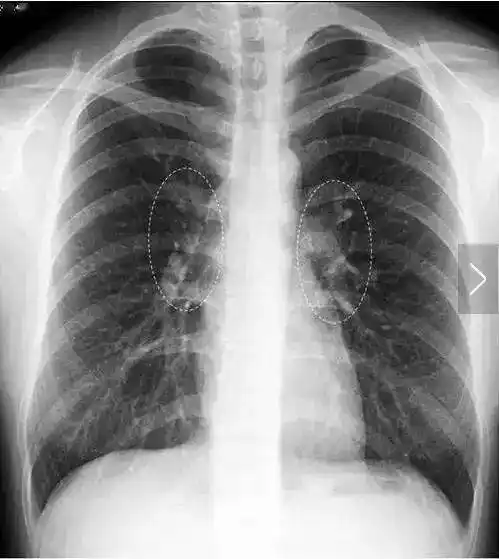

左,右肺门(虚线椭圆范围内)为肺动静脉及气管